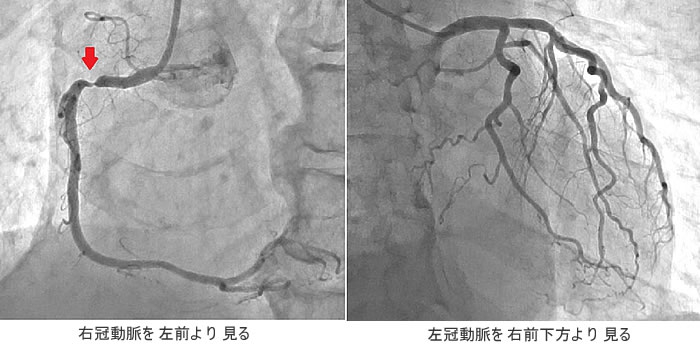

右冠動脈に狭窄病変(上左図の矢印部)があることがわかります。左冠動脈には目立った異常はなさそうです。(上右図)左右の冠動脈に対していろいろな方向から撮影を繰り返し、全体像を作り上げるわけです。